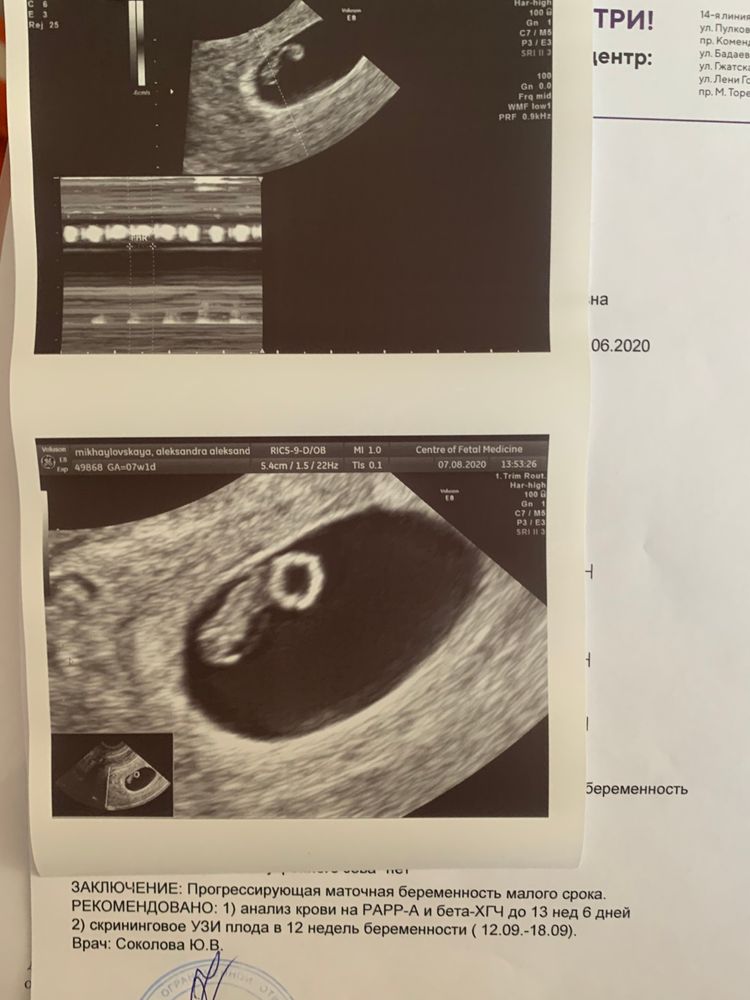

Развитие эмбриона на 8 неделе беременности